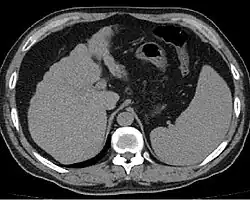

Liver cirrhosis on CT imaging of the abdomen in transverse view

Imaging

Ultrasound is routinely used in the evaluation of cirrhosis.[45] It may show a small and shrunken liver in advanced disease. On ultrasound, there is increased echogenicity with irregular appearing areas.[64] Other suggestive findings are an enlarged caudate lobe, liver surface nodularity[65] widening of the fissures and enlargement of the spleen.[66] An enlarged spleen, which normally measures less than 11–12 cm (4.3–4.7 in) in adults, may suggest underlying portal hypertension.[67] Ultrasound may also screen for hepatocellular carcinoma and portal hypertension.[45] This is done by assessing flow in the hepatic vein.[68] An increased portal vein pulsatility may be seen. However, this may be a sign of elevated right atrial pressure.[69] Portal vein pulsatility is usually measured by a pulsatility index (PI).[68] A number above a certain value indicates cirrhosis (see table below).

Other scans include CT of the abdomen and MRI.[45] A CT scan is non-invasive and may be helpful in the diagnosis.[45] Compared to the ultrasound, CT scans tend to be more expensive. MRI provides excellent evaluation; however, it is expensive.[45]